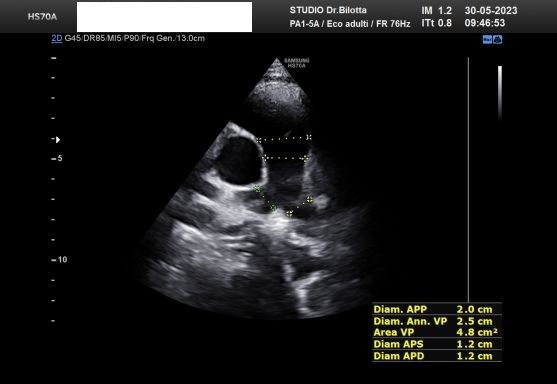

Diploma di maturità classica. Laurea in Medicina e Chirurgia con Lode a 26 anni. Specialista in Oncologia Generale Diagnostica e Preventiva con Lode a 31 anni. Specialista in Malattie Cardiovascolari a 36 anni. Medico generalista dal 1990 poi ospedaliero per trent'anni dal 1993 al 2022 nel corso dei quali ho refertato oltre 100 mila tracciati elettrocardiografici, effettuato oltre 30 mila consulenze specialistiche, praticato circa 10 mila esami ecocardiografici, condotto oltre 2 mila test ergometrici sia su cicloergometro che su treadmill, visionato circa 1500 esami Holter Ecg e ABP ( Ambulatory Blood Pressure ) occupandomi prevalentemente di prevenzione cardiovascolare, ipertensione arteriosa, cardiopatia ischemica, valvulopatie. Dal 2023 ho deciso di trasferire le mie competenze nella libera professione presso il mio studio privato che è stato allestito in linea alle moderne esigenze tecnologiche. Metodiche diagnostiche attualmente praticate: Elettrocardiografia a riposo, Ecocardiografia mono-bidimensionale, PW, CW, Colordoppler tridimensionale, GLS Strain Speckle tracking, Monitoraggio Holter Pressorio delle 24 ore, Monitoraggio Holter ECG 12 canali dinamico delle 24 ore.

Foto e video